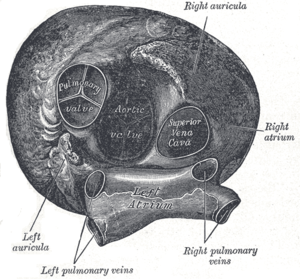

Pulmonary circuit Heart seen from above.

Heart seen from above. Transverse section of thorax, showing relations of pulmonary artery.